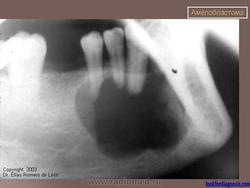

Амелобластома

ID: 13276 Ameloblastoma Dr Morlie L Wang - 21 Mar 2011 Pathologically proven ameloblastoma.